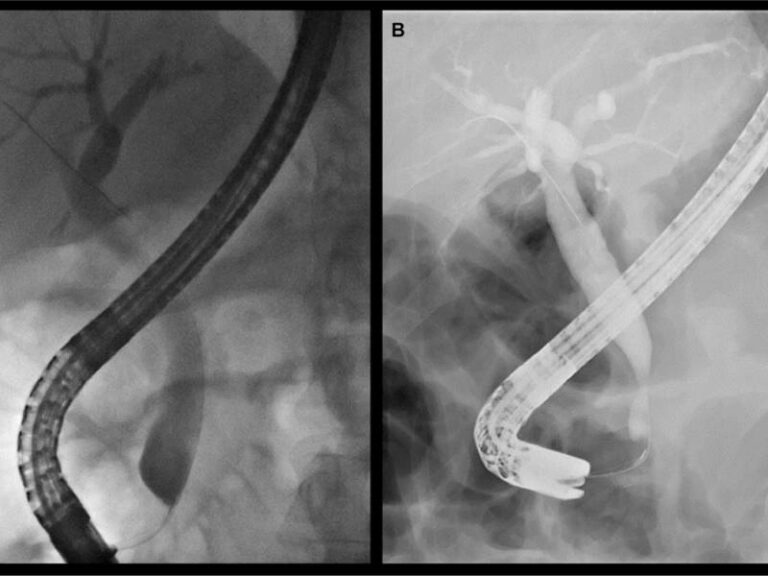

From www.researchgate.net

ERCP films show the proximal common bile duct stricture and dilated... Download Scientific Diagram Duct Stricture Definition Bile ducts are tiny canals that connect some of the organs in your digestive system. A stricture in this area prevents the free. This is a tube that moves bile from the liver to. Like stenosis, the word stricture also refers to the narrowing of a passageway in your body. What is a bile duct? A bile duct stricture is. Duct Stricture Definition.